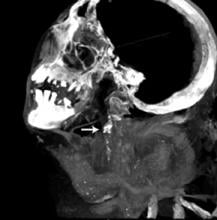

New research published in the June issue of Global Heart, the journal of the World Heart Federation, shows that there are no significant differences in the incidence or severity of atherosclerotic disease (narrowing of the arteries with fatty deposits) between ancient and modern people, proving that atherosclerosis is not just a disease of modern times. The journal included three articles [1,2,3] on the finding of the Horus study, which used computed tomography (CT) scans from ancient mummies to compare arterial calcification caused by Horus atherosclerosis.